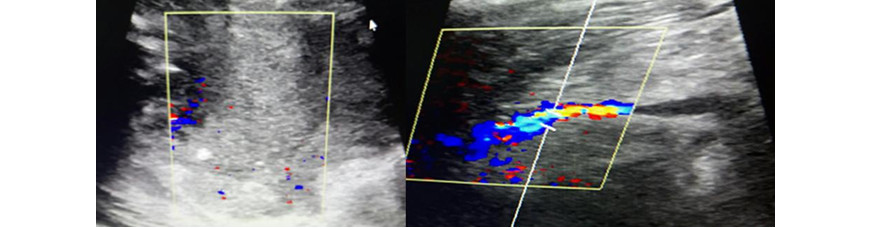

En la ecografía de partes blandas y el ultrasonido Doppler venoso del miembro inferior derecho se observó una masa multilobulada, de composición heterogénea y contornos irregulares, que comprimía el sistema venoso profundo. No hubo hallazgos sonográficos de trombosis venosa profunda (Fig. 2).

Fig. 2 - Ecografía de partes blandas y ultrasonido Doppler venoso del miembro inferior derecho: Obsérvese la masa heterogénea, mal definida, que comprime el sistema venoso profundo.